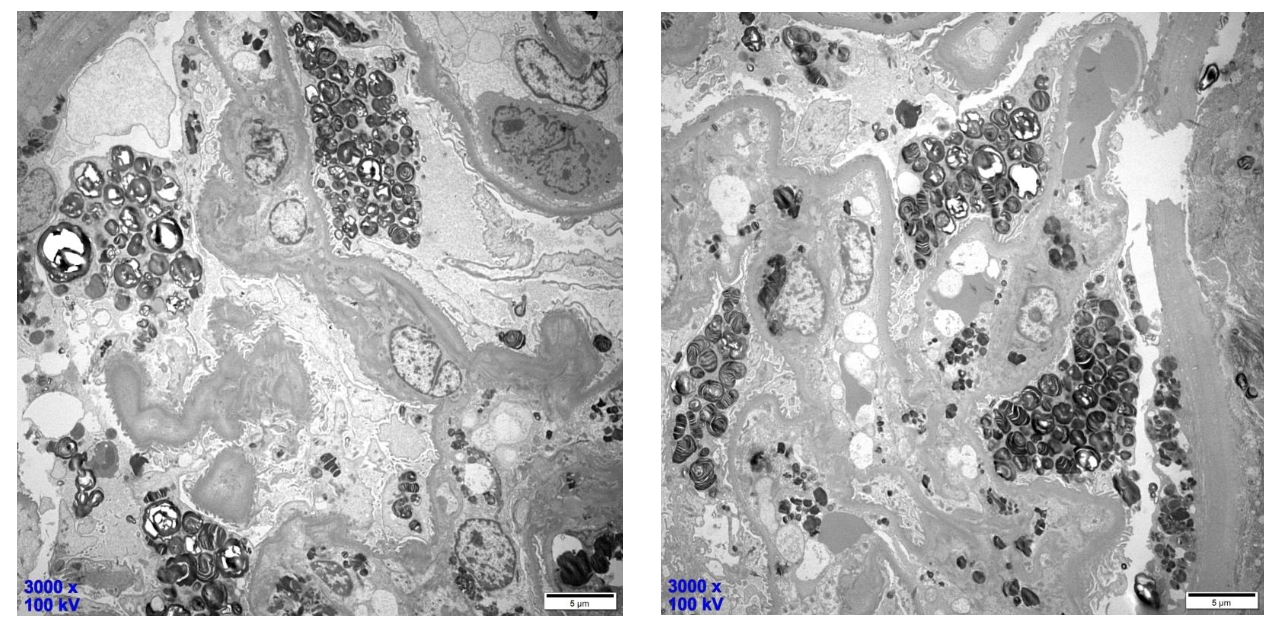

电镜表现

电镜标本经甲苯胺蓝染色,可见1个肾小球,可见嗜甲苯胺蓝颗粒在足细胞、小管上皮细胞以及壁层上皮细胞多部位沉积;

超薄切片电镜下观察,毛细血管襻开放,壁层细胞无明显增生。基底膜无明显增厚,厚度约250-450nm;

部分足细胞空泡变性,呈泡沫状,次级溶酶体增多并见大量髓样小体和斑马小体,足突弥漫性融合;

上皮下未见电子致密物沉积,系膜细胞和基质无增生,系膜细胞胞浆可见少许电子致密物沉积,内皮下未见确切电子致密物沉积。肾小管上皮细胞空泡变性,肾间质无特殊病变;

电镜下具有特征性改变,即肾脏各种细胞的细胞质内均可充满嗜锇“斑马小体”。(以上两张图组)

该“斑马小体”呈较高电子密度,圆形或卵圆形,直径1~5um,小体内部呈层状,层间距较一致,形似斑马皮,亦似洋葱皮、层状结构或髓鞘样结构,故称“斑马小体”“洋葱皮小体”“片层样小体”或“髓样小体”,当该小体被包含在溶酶体中,周围由一层膜包绕,为Fabry病特征性表现。(以上两张图组)

各种细胞的细胞质内均可见,包括肾小球脏层上皮细胞、壁层细胞、肾小管上皮细胞、肾间质细胞、血管壁内皮细胞和平滑肌细胞(以上六张图组)